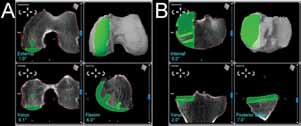

Fig. 4 Intraoperative screenshots of the robotic system showing the computer model of any anatomy based on preoperative CT-scans and allowing for precise positioning of the femoral (A) and tibial (B) components. |

Historically, UKA has been considered a technically demanding procedure that poses a challenge to the orthopaedic surgeon. More recently, the development and use of robotic-assisted technology[74] has made performing UKA technically less demanding and various studies have reported improved radiographic outcomes, more consistent component placement, and fewer outliers[26] (Figure 4).

For example, Bellemans et al. reported implant positioning and alignment to fall within 1° error of neutral alignment for all cases performed with robotic-assistance.[75] Furthermore, Cobb et al. demonstrated that the number of radiographic outliers following UKA decrease significantly with the aid of robotic systems.[26] However, the results of this study should be interpreted with caution, as it remains unclear if these more favorable radiographic outcome measures correlate with greater functional improvement.[26,76 ]

Computer assisted surgery systems, also called passive surgery systems, monitor operative procedures and allow for intraoperative assessment and feedback during adult reconstructive surgery (Figure 5).[67,74,77]

The individual design of passive surgery systems is proprietary, however, these systems track various parameters (i.e. component positioning, bone geometry) during operative procedures.[78] Computer-based intraoperative systems may offer greater accuracy over conventional templating methods, thus, passive systems may be utilized during UKA to more accurately and precisely place components.[66,77,78] Better component placement during UKA has been associated with clinical success.[37,67,77, 78,79] Specifically, Pearle et al. and Cobb et al. found that intraoperative computerguidance enabled component positioning to within 2° of the preoperative plan in all cases.[26,37] In these studies, up to 60% of UKA components were determined to be improperly positioned when computer navigation was not used.[26,37] Other studies have reported that femoral and tibial component alignment, tibial slope, and lower extremity mechanical axis was improved when passive surgery systems were used during UKA.[80-85]

Robotic systems have also been designed to aid surgeons during UKA. Using templates prepared from a computer-tomography scan, the robot provides both tactile and haptic response during the procedure in order to assist the surgeon in matching their preoperative plan. Ligament balancing and range of motion are also obtained intraoperatively with the UKA prosthesis in place. Early reports of radiographic outcomes have been promising when the robotic system has been utilized.[61,86,87] Lonner et al. conducted a radiographic comparison of 31 consecutive patients who underwent roboticassisted UKA to 27 consecutive patients who underwent manual UKA.[86] The authors found that there was almost three times greater variation in tibial component using the standard method, suggesting that robotic-assisted surgery leads to more consistent component placement. However, these findings have not been correlated to clinical outcomes. Additionally, Roche et al. reported on the one-year outcomes of 223 robot-assisted UKAs.[87] At the most recent follow-up, none of the patients required revision surgery and there was a statistically significant improvement in clinical outcome scores. However, until mid-term results are available, many institutions will find it hard to invest in this new technology.